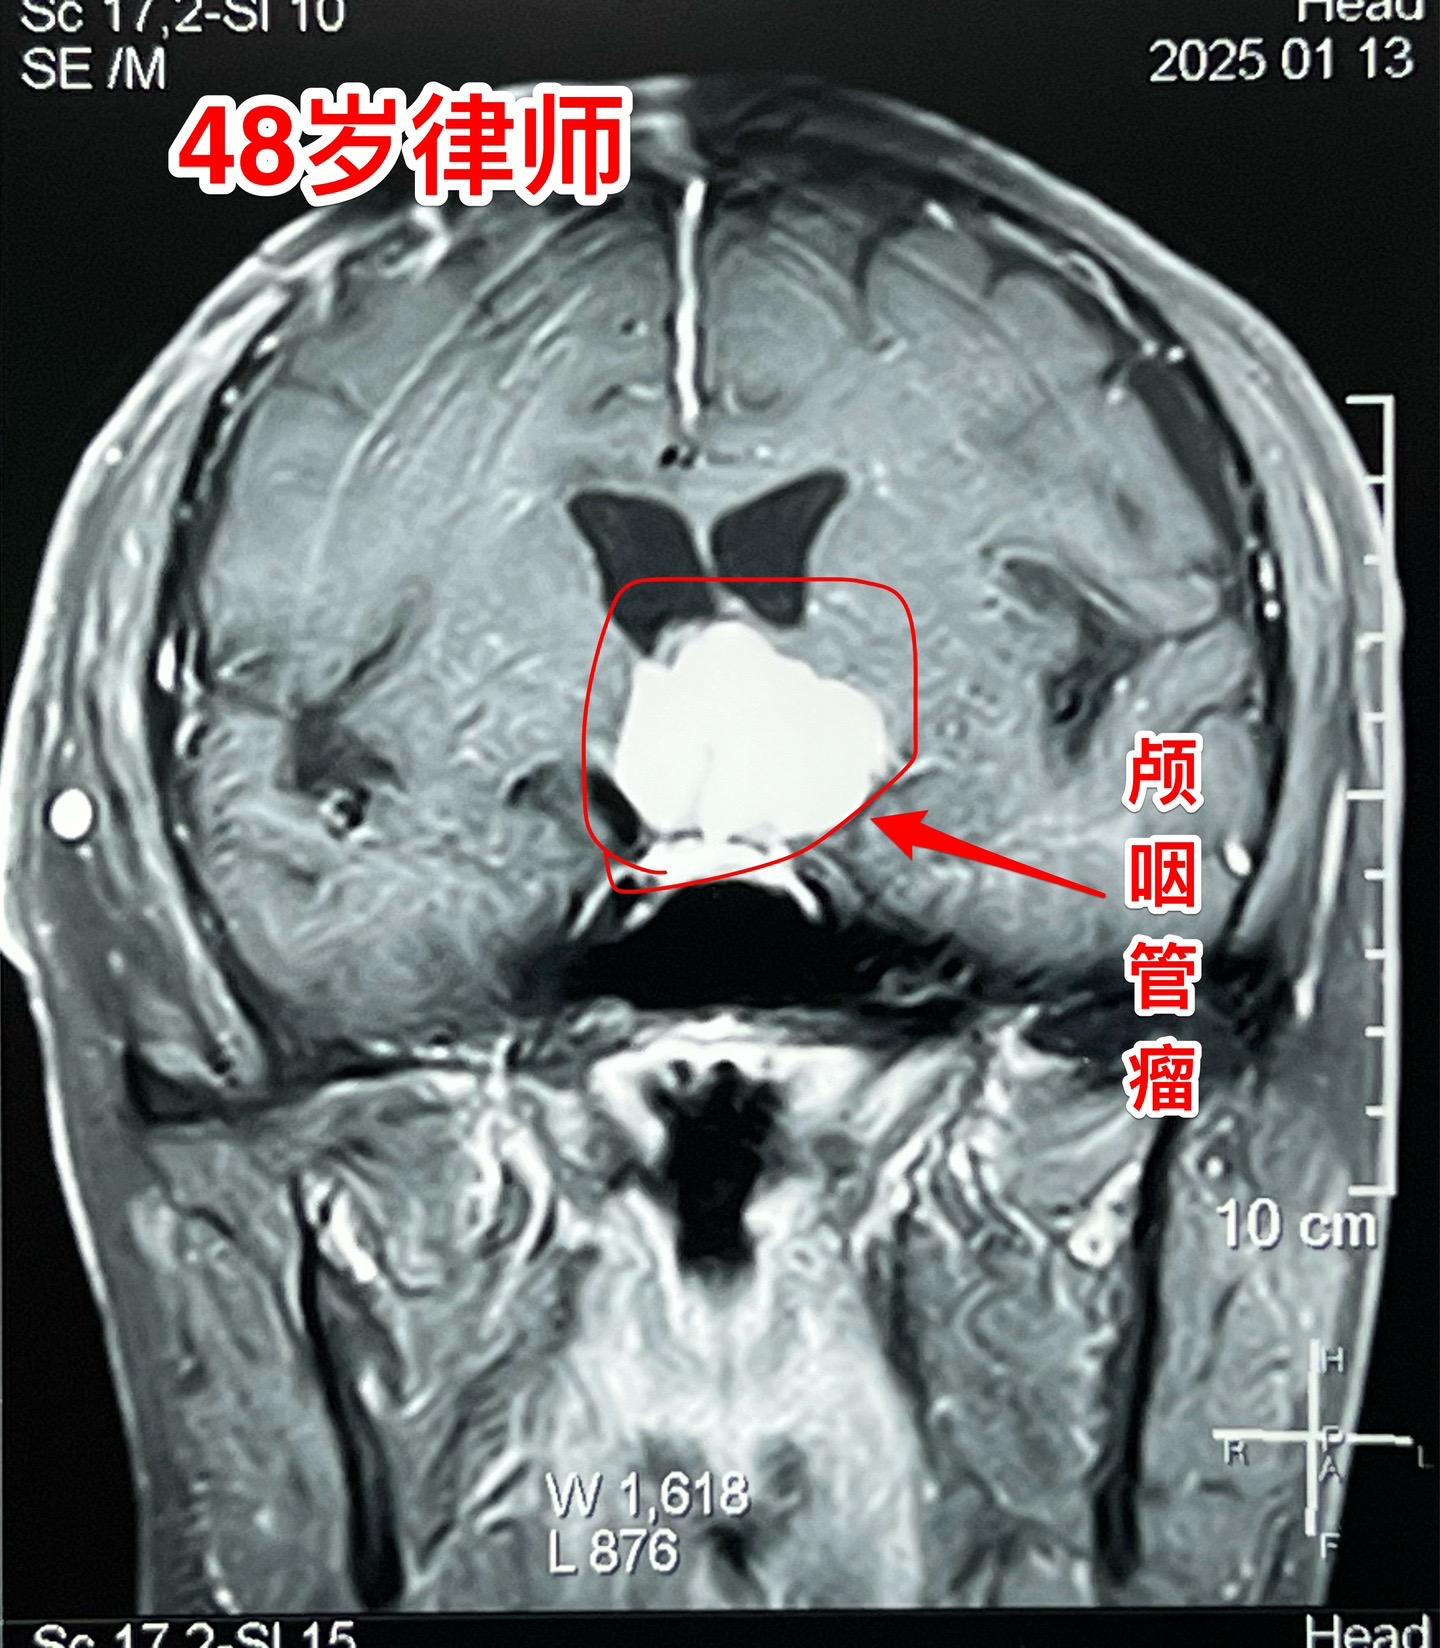

48岁律师,颅咽管瘤术后三个月复查。律师在四川凉山工作,在四川某医院手术未满三个月,自手术后就有记忆力差、爱睡觉等体积症状,难以胜任律师工作。复查磁共振显示颅咽管瘤体积仍然很大,怀疑为肿瘤复发了。 患者家人治病心切,直接到北京找我做手术。 今天是腊月二十四,还有5天就过年了。今天为律师作了开颅手术,将肿瘤完全切除了。希望颅咽管瘤不再复发。